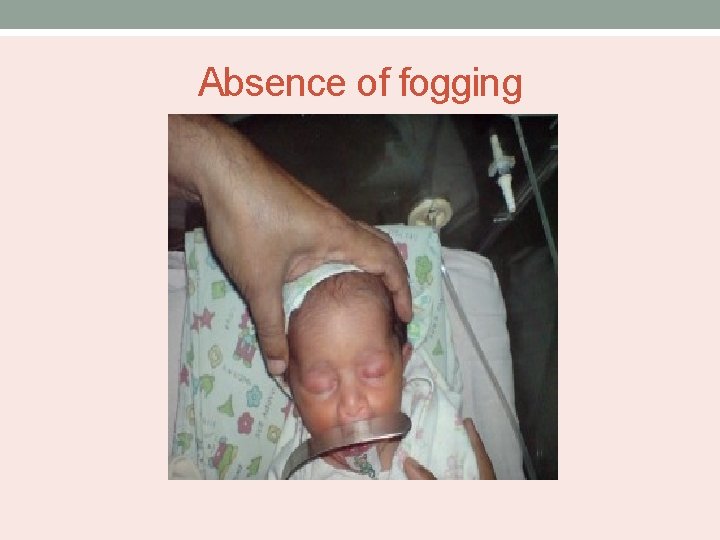

Absence of fogging